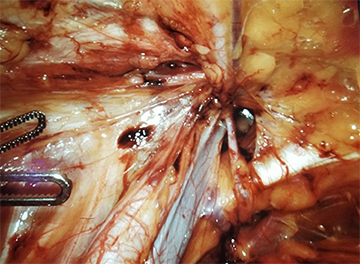

Visualization of the critical view of the left myopectineal orifice during robotic left femoral hernia repair

(Courtesy of Dr. Yuri Novitsky)